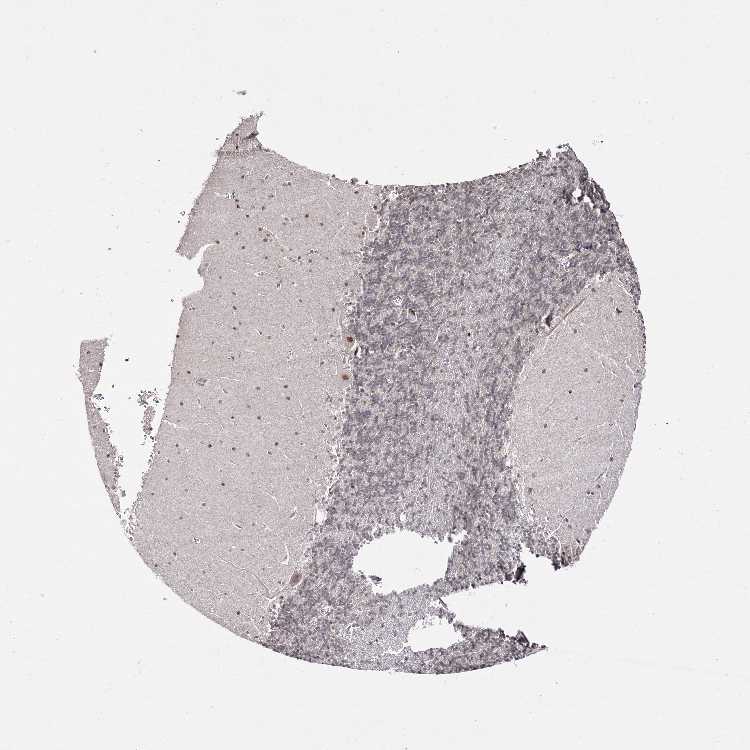

CEREBELLUM - Antibody stainingi

Antibody staining in the annotated cell types in the current human tissue is reported as not detected, low, medium, or high, based on conventional immunohistochemistry profiling in selected tissues. This score is based on the combination of the staining intensity and fraction of stained cells.

Each image is clickable and will lead to virtual microscopy that enables deeper exploration of all samples and also displays staining intensity scores, fraction scores and subcellular localization as well as patient and tissue information for each sample.

Antibody HPA037845

Purkinje cells Medium

Cells in granular layer Not detected

Cells in molecular layer Medium